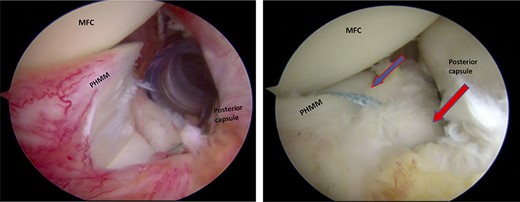

A posteromedial portal was utilized to repair both ramp tears using all-inside sutures, and curved suture hooks were inserted through the posteromedial portal. The first tear was repaired, and a non-absorbable suture was passed between the peripheral edge of the PHMM and attachment of the meniscotibial ligament (Fig. 6). The second tear was then repaired by passing the suture through the posterior capsular tissue, creating a bridge between the two tears to restore the meniscocapsular attachment (Fig. 7).

Trans-notch view of the postromedial compartment of the left knee showing the repair of both ramp lesion tears. The blue arrow indicates the repair of the first lesion at the meniscosynovial junction of the red-red zone area. The red arrow indicates the repaired second tear at the meniscocapsular attachment. PHMM, posterior horn of medial meniscus; MFC, medial femoral condyle